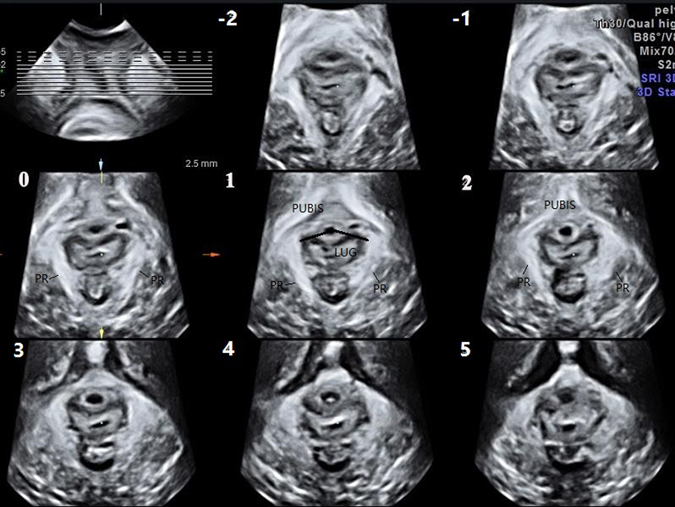

Figure 1.

Images of the normal levator ani muscle of a 20-year-old nulliparous woman on TUI are presented. The image in the top left corner is a reference slice in the coronal plane. The other eight images represent axial plane slices obtained at 2.5-mm intervals; slice 1 is obtained in the plane of the minimum levator hiatus; the -1, -2, and 0 slices are caudal of the minimum plane; and the 2, 3, 4, and 5 slices are cephalad of the minimum plane. LUG was measured in slices 0, 1, and 2 and then averaged. (TUI: Tomographic ultrasound imaging; LUG: Levator-urethra gap, PR: puborectalis).

Translabial ultrasound was performed on these women in a supine position after voiding using the GE Voluson E8 system (GE Kretz technik GmbH, Zipf, Austria) with an RAB 4–8 MHz transducer. Volume datasets were acquired at rest on maximum pelvic floor muscle contraction and maximum Valsalva. Each patient performed at least 3 Valsalva manoeuvres, and the best one was used for the evaluation. Volumes obtained on maximum pelvic floor muscle contraction were particularly useful, as defects seemed to become more defined on contraction of the muscle23. Using TUI, a set of 8 parallel tomographic slices was obtained in the axial plane at intervals of 2.5 mm from 5.0 mm caudal to 12.5 mm cephalad of the plane of minimum levator hiatus (Fig. 1). Puborectalis avulsion was identified at the plane slices 0, 1, and 2 on maximum pelvic floor muscle contraction21. Avulsion was recorded as left, right or bilateral. In this study, avulsion was defined as no muscle remaining on slices 0, 1, 2 of TUI. The measurement of the levator-urethra gap (LUG) was taken by placing callipers on the centre of the hypoechogenic structure that indicated the urethral mucosa and smooth muscle and on the most medial aspect of the muscle insertion. LUG was measured in three slices and then averaged. The images were analysed separately by 2 senior authors with abundant experience in diagnosing levator avulsion, but they were blinded to each other. If different results occurred, they consulted to make a decision.